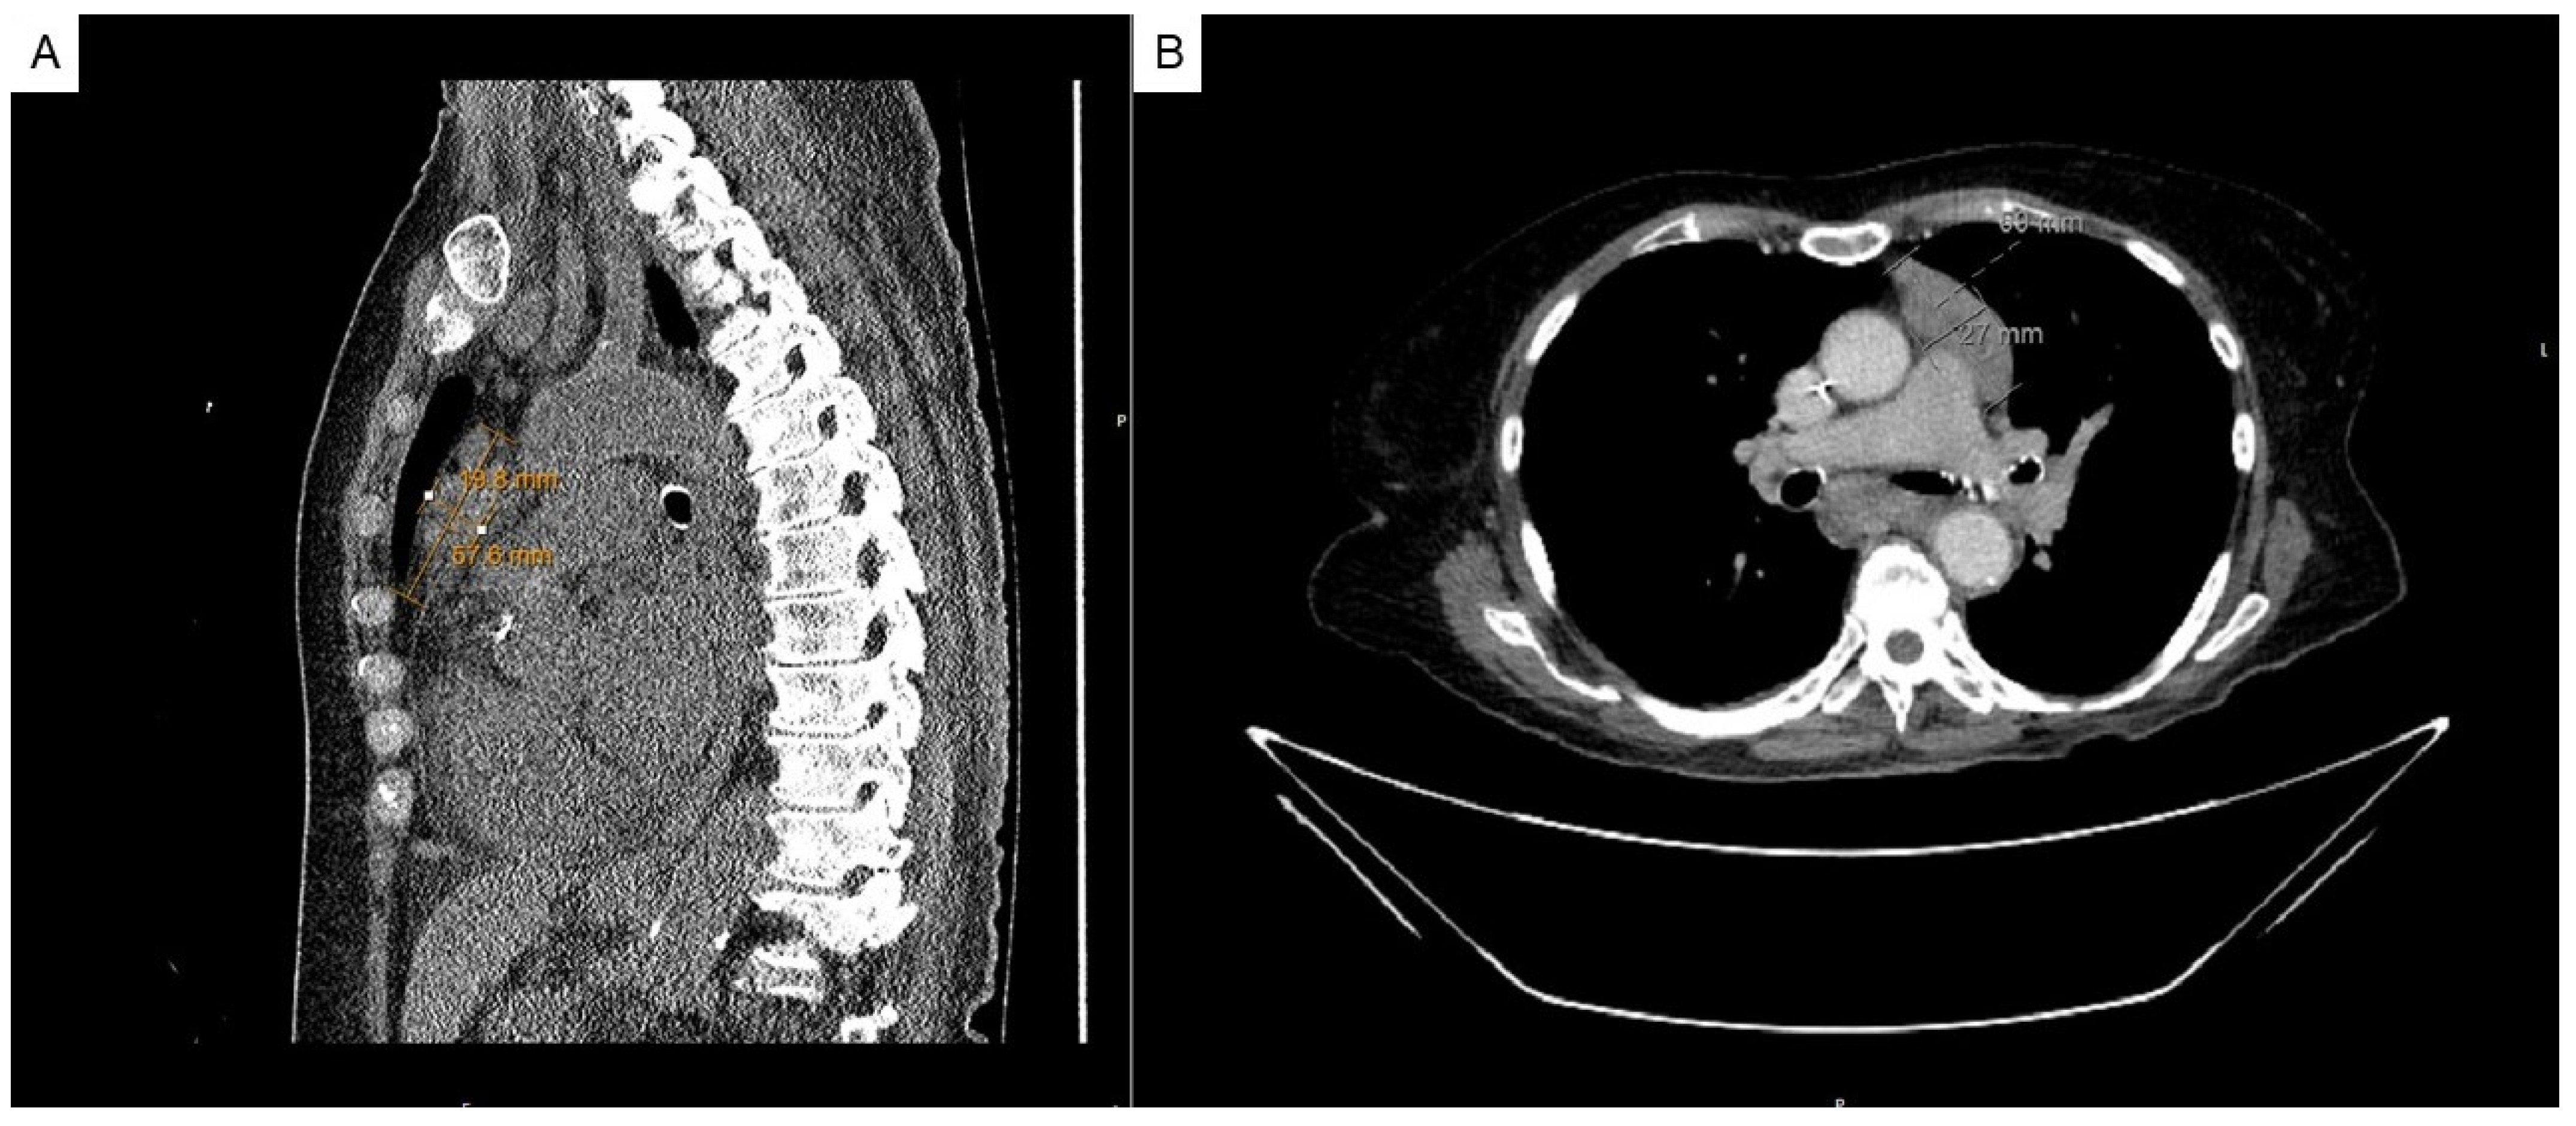

2. Case Presentation